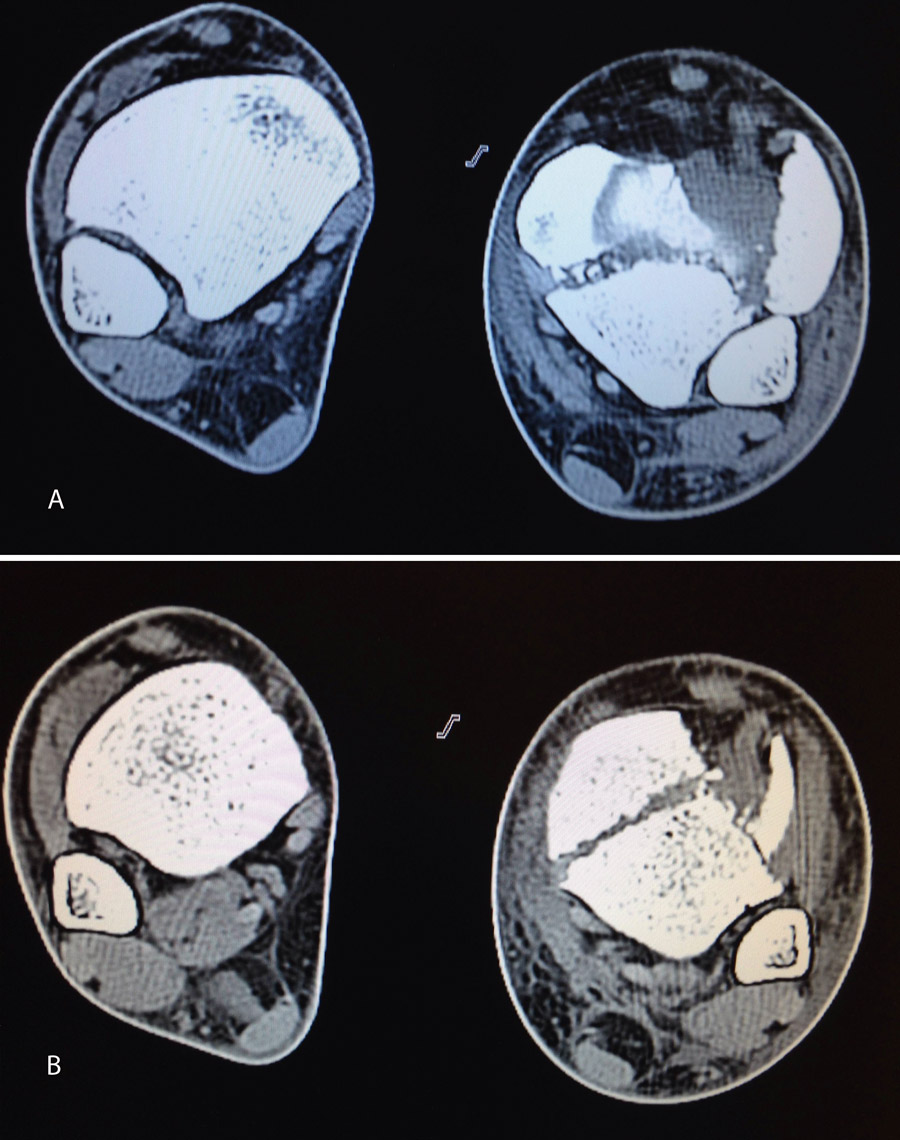

En este caso, es esencial observar las Rx con y sin tracción que nos indican cómo se va a comportar la fractura. Si la fractura es reductible en tracción, es muy probable que podamos realizar una osteosíntesis con restitución completa de la superficie articular. Al realizar la TC, apreciamos la disposición de los fragmentos para marcar una estrategia de reducción bajo control radioscópico y artroscópico, y colocación de los tornillos canulados que fijarán la epífisis distal de la tibia.

Figura 18. La tomografía computarizada muestra los fragmentos principales de la fractura, estando desplazado el Tillaux que se reduce con la tracción.